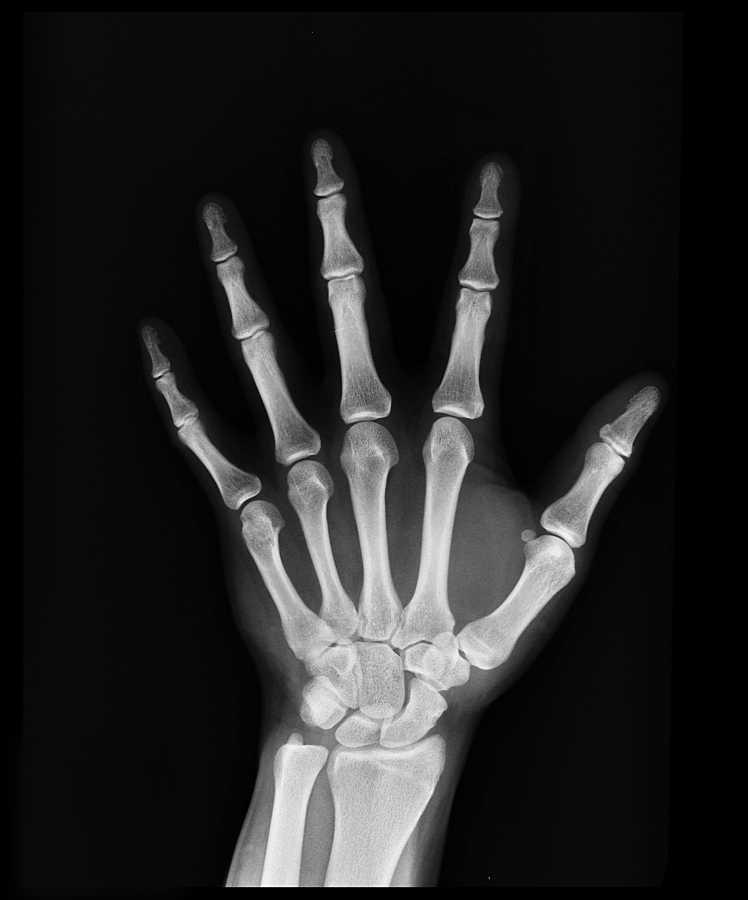

Radiografía de la mano afectada.